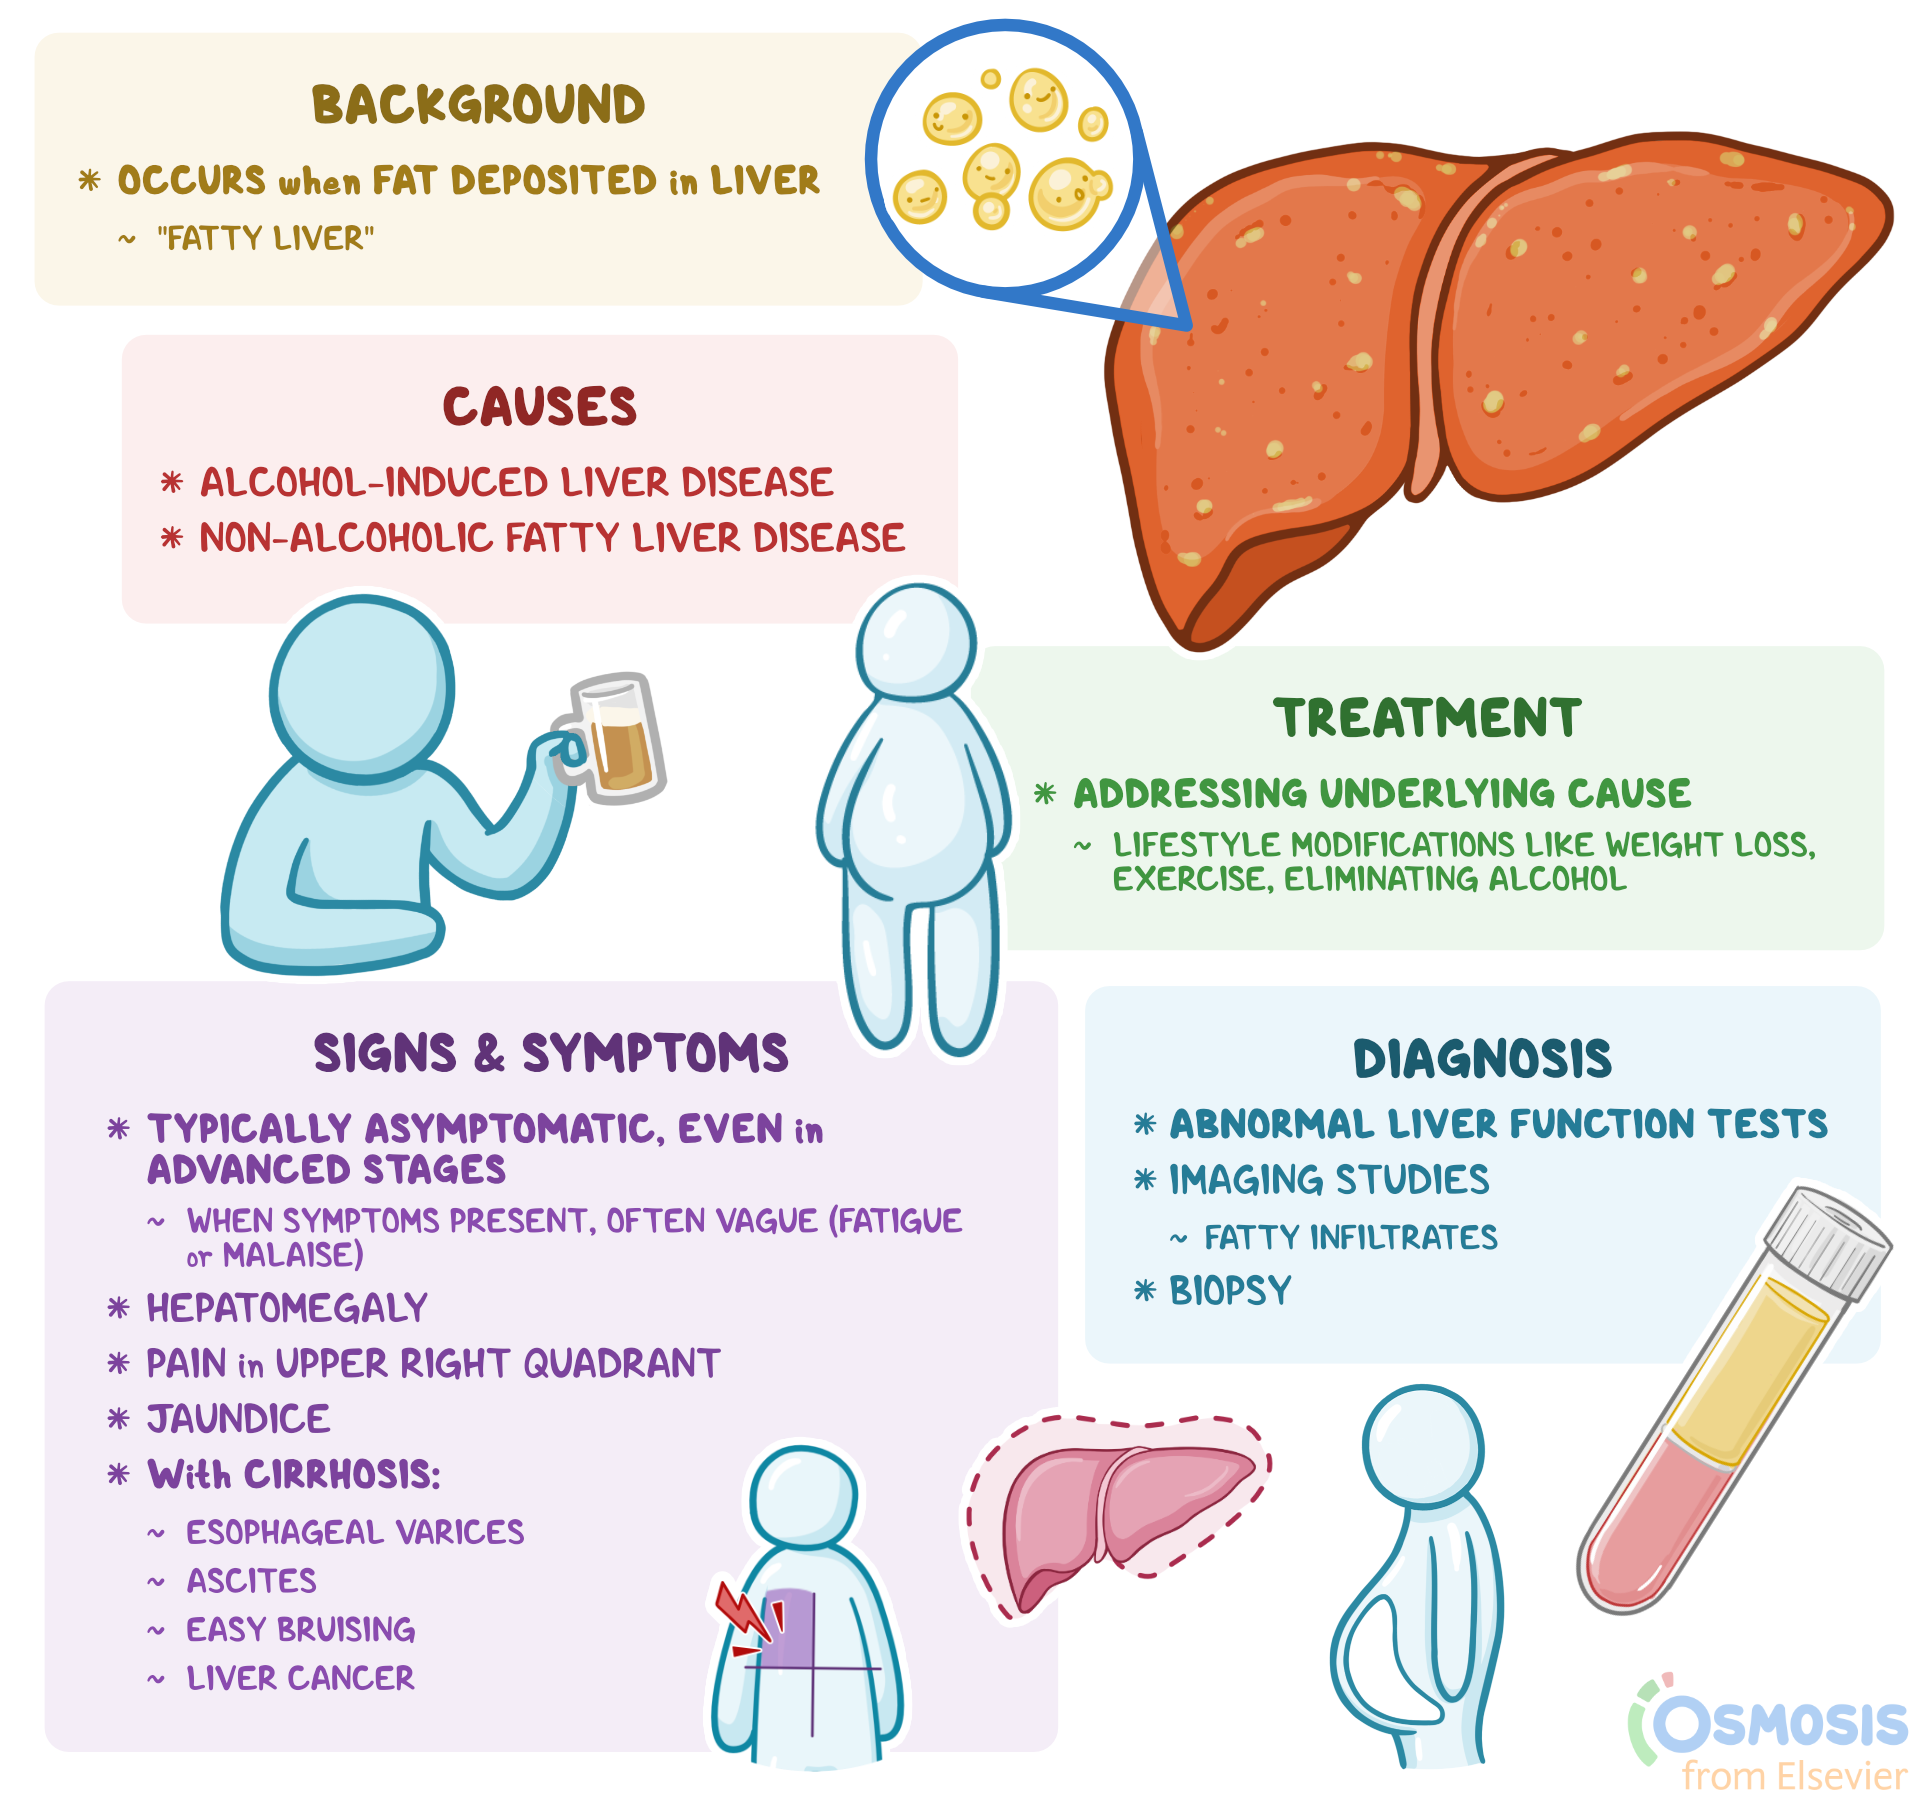

Hepatic Steatosis What Is It Causes Diagnosis Treatment And More